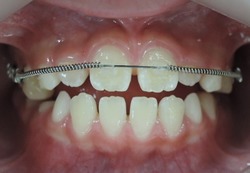

☆上顎から矯正装置を装着していきます。

☆上顎の歯が揃ってから、下額に矯正装置(ブラケット)を装着します。

☆終了時(1年6ヶ月)